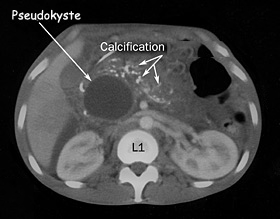

L'abdomen sans préparation peut montrer des calcifications pancréatiques (Figure n°1).

Le scanner est l’examen de première intention et de référence. La phase sans injection permet de faire le diagnostic de calcifications pancréatiques. Il montre les complications comme les pseudokystes (

Figure n°2).

Figure n°1 et 2 : Calcifications pancréatiques sur un ASP et un Scanner